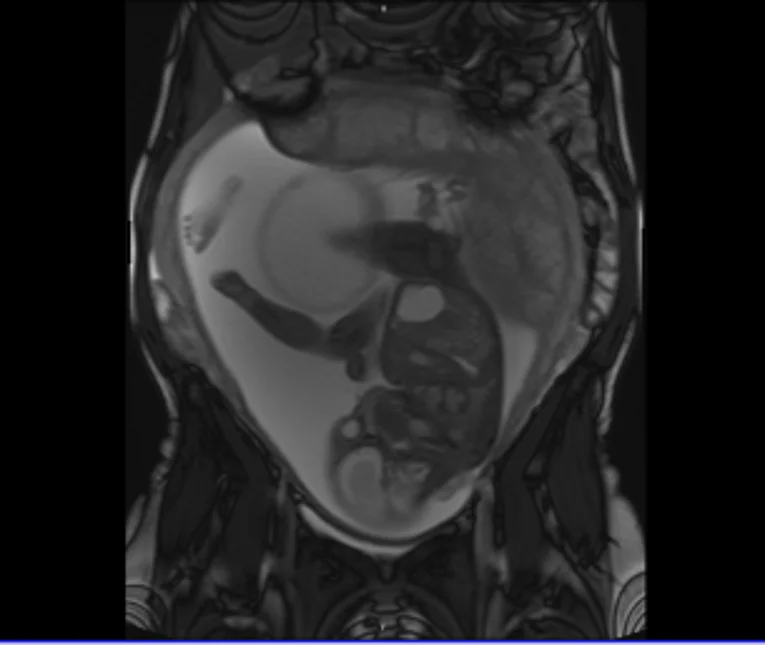

Das Steißbeinteratom ist ein uneinheitlicher (heterogener) Keimzelltumor aus vielen verschiedenen Zell- und Gewebearten. Man unterscheidet gutartige (reife) Tumoranteile, bei denen die Tumorzellen zu anderen im Körper vorkommenden Zellarten ausdifferenziert sind (z. B. Drüsengewebe, Nervenzellen, Knochen) von bösartigen (unreifen) Tumoranteilen, bei denen die Tumorzellen keinem körpereigenen Gewebe gleichen. Der Tumor haftet dem Steißbein fest an und erhält seine Blutversorgung über eigene Blutgefäße aus dem kleinen Becken. Es können äußerlich der Steißregion aufsitzende sowie nach innen ins Becken reichende Tumoranteile vorliegen. Steißbeinteratome können eine beachtliche Größe erreichen.

Häufig wird das Steißbeinteratom bereits während der Schwangerschaft in den Ultraschallvorsorgeuntersuchungen erkannt und dann regelmäßig kontrolliert. In enger Zusammenarbeit mit den Kolleginnen und Kollegen der Frauenklinik und der Kinderklinik führen wir Beratungsgespräche mit den werdenden Eltern vor der Entbindung durch. Die Entbindung wird in der Regel per Kaiserschnitt geplant, um ein Einreißen des Tumors während einer spontanen Geburt zu verhindern. Die Erstversorgung des Neugeborenen übernehmen die Kinderärztinnen und -ärzte der Früh- und Neugeborenenstation (Neonatologie). Die Operation wird dann nach sorgfältiger Vorbereitung in den ersten 72 Lebensstunden geplant. Neben der vollständigen Tumorentfernung ist hierbei insbesondere die Rekonstruktion des Gesäßes und Beckenbodens von besonderer Bedeutung. Nach dem Eingriff erfolgt die weitere Überwachung auf der Neonatologie.